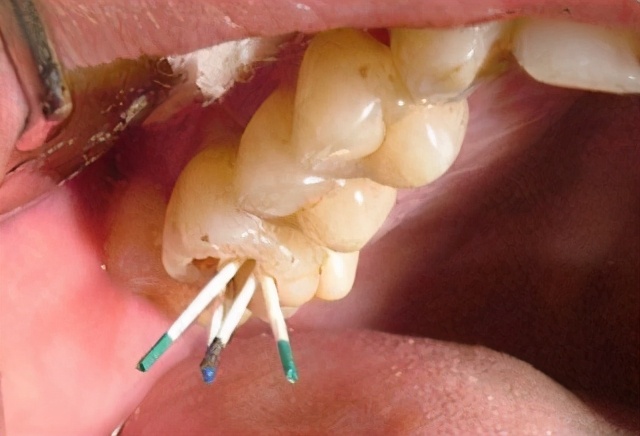

3.根尖周炎引起的牙痛

这是因为牙齿的根尖策划出现急性或慢性炎症,导致牙痛!这种痛苦将继续,但范围有限,也就是说,无论哪里有坏牙,都会疼,并且可以准确地找到坏牙!可以使用赤通消炎灵颗粒。如果患者脸颊肿胀,疼痛,化脓和发烧,应该去医院!